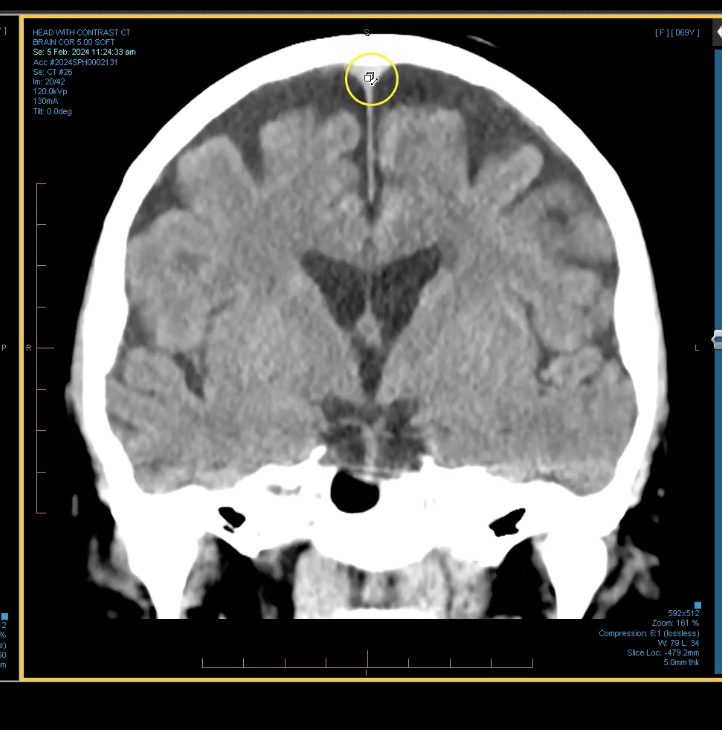

term image

lateral ventricles